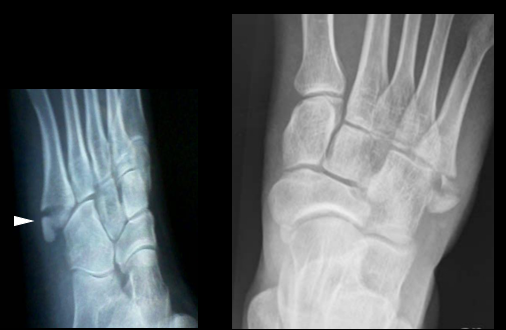

Lawrence 等根据骨折部位把第五跖骨近端骨折分为3区(最常用):

• Ⅰ区:骨折是跖骨粗隆部撕脱骨折,发生率最高;

• 区:骨折是干骺端与骨干连接部骨折,又称Jones骨折,因血运原因容易发生不愈合;

• III区:骨折是跖骨干部的疲劳骨折,多见于运动员

第五跖骨Ⅰ区骨折分型:Ekrol等把第五跖骨Ⅰ区骨折按部位从近而远又分为3个类型:(如图所示)

• 1型:是粗隆尖部骨折;

• 2型:是从第五跖骨基底到第五跖骨-骰骨关节面的斜形骨折;

• 3型:是通到第四跖骨关节面的横行骨折。